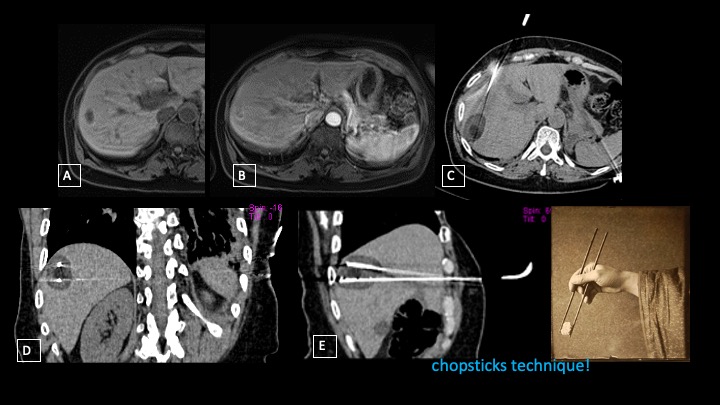

Our patient was a 67-year-old man with a single 2-cm liver metastasis in the right lobe derived from colorectal cancer. Fat-suppression-weighted T1 acquired before and after contrast media injection showed a well-defined hypointense lesion with a peripheral contrast enhancement border (Figures 1A, 1B). The patient was considered unsuitable for surgery or chemotherapy. The tumor board decided on a percutaneous ablative approach.

The metastasis was located a short distance from the hepatic margin, so cryoablation was chosen as the ablation method instead of other ablative methods such as radiofrequency or microwave ablation.

With the patient supine, 2 cryoprobes were inserted by anterior approach, and placed almost parallel in a chopsticks formation immediately above and below the lesion, in order to encase the metastasis and create a safety margin around the lesion.1

Of note, the lateral and posterior approach was not chosen to reduce the risk of unwanted puncture of the pleura and subsequent potential pneumothorax. In addition, the distance between the 2 probes was about 15 mm to optimize the synergy of action of the 2 ice balls.

At the conclusion of the freezing phase, axial, coronal, and sagittal computed tomography reconstruction (Figures 1C, 1D, 1E) showed the tumor (central hypodensity) and the ice ball as hypodensity around the tumor, enlarging the ablation area by 5/10 mm, corresponding to the safety zone.